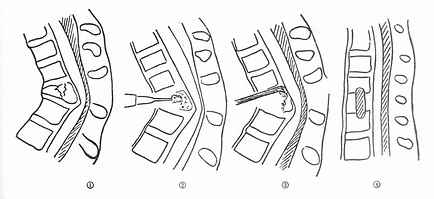

(五)切片状骨折的治疗 因为这种骨折伴有整个韧带的完全撕裂,且常合并截瘫,用Harrington撑开棍治疗后方间隙反而会明显增宽。应选用强度较好的Luque或Dick装置为好,不仅能获得满意的复位(图73-16①~③),而且固定牢固,术后即可随意翻动病人,术后1-2即可让病人起床坐轮椅活动,有利于截瘫病人的康复与护理。

图73-16 切片骨折的治疗